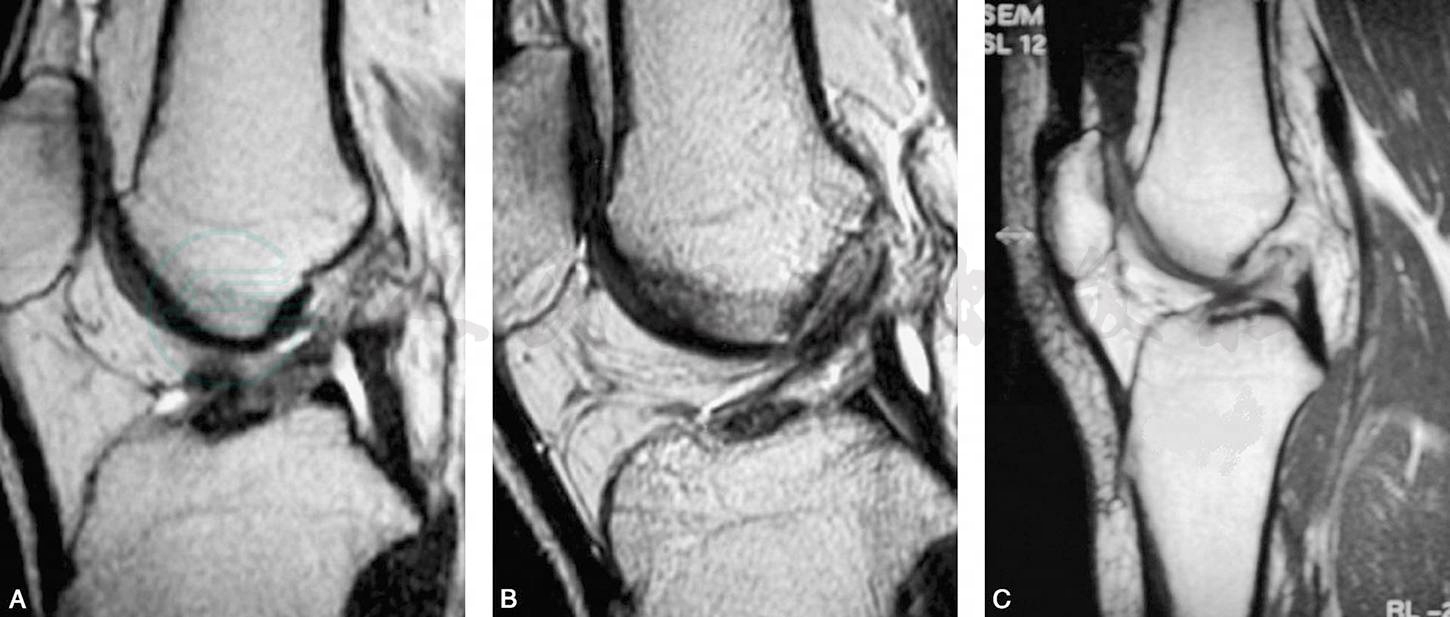

前交叉韧带慢性损伤的磁共振影像表现为三种情况:信号消失、信号不规则和信号移位。前交叉韧带损伤后韧带组织被完全吸收,磁共振成像上则表现为信号消失(图11A)。

前交叉韧带损伤后有残存的少量纤维和瘢痕组织被滑膜包绕,即为信号不规则,它包括信号密度不均、粗细不均、迂曲无张力等(图11B)。

信号移位是指前交叉韧带自股骨止点撕脱后瘢痕粘连在后交叉韧带上(图11C)。

图11前交叉韧带慢性损伤的磁共振成像

A.前交叉韧带信号消失;B.前交叉韧带信号不规则;C.前交叉韧带信号移位